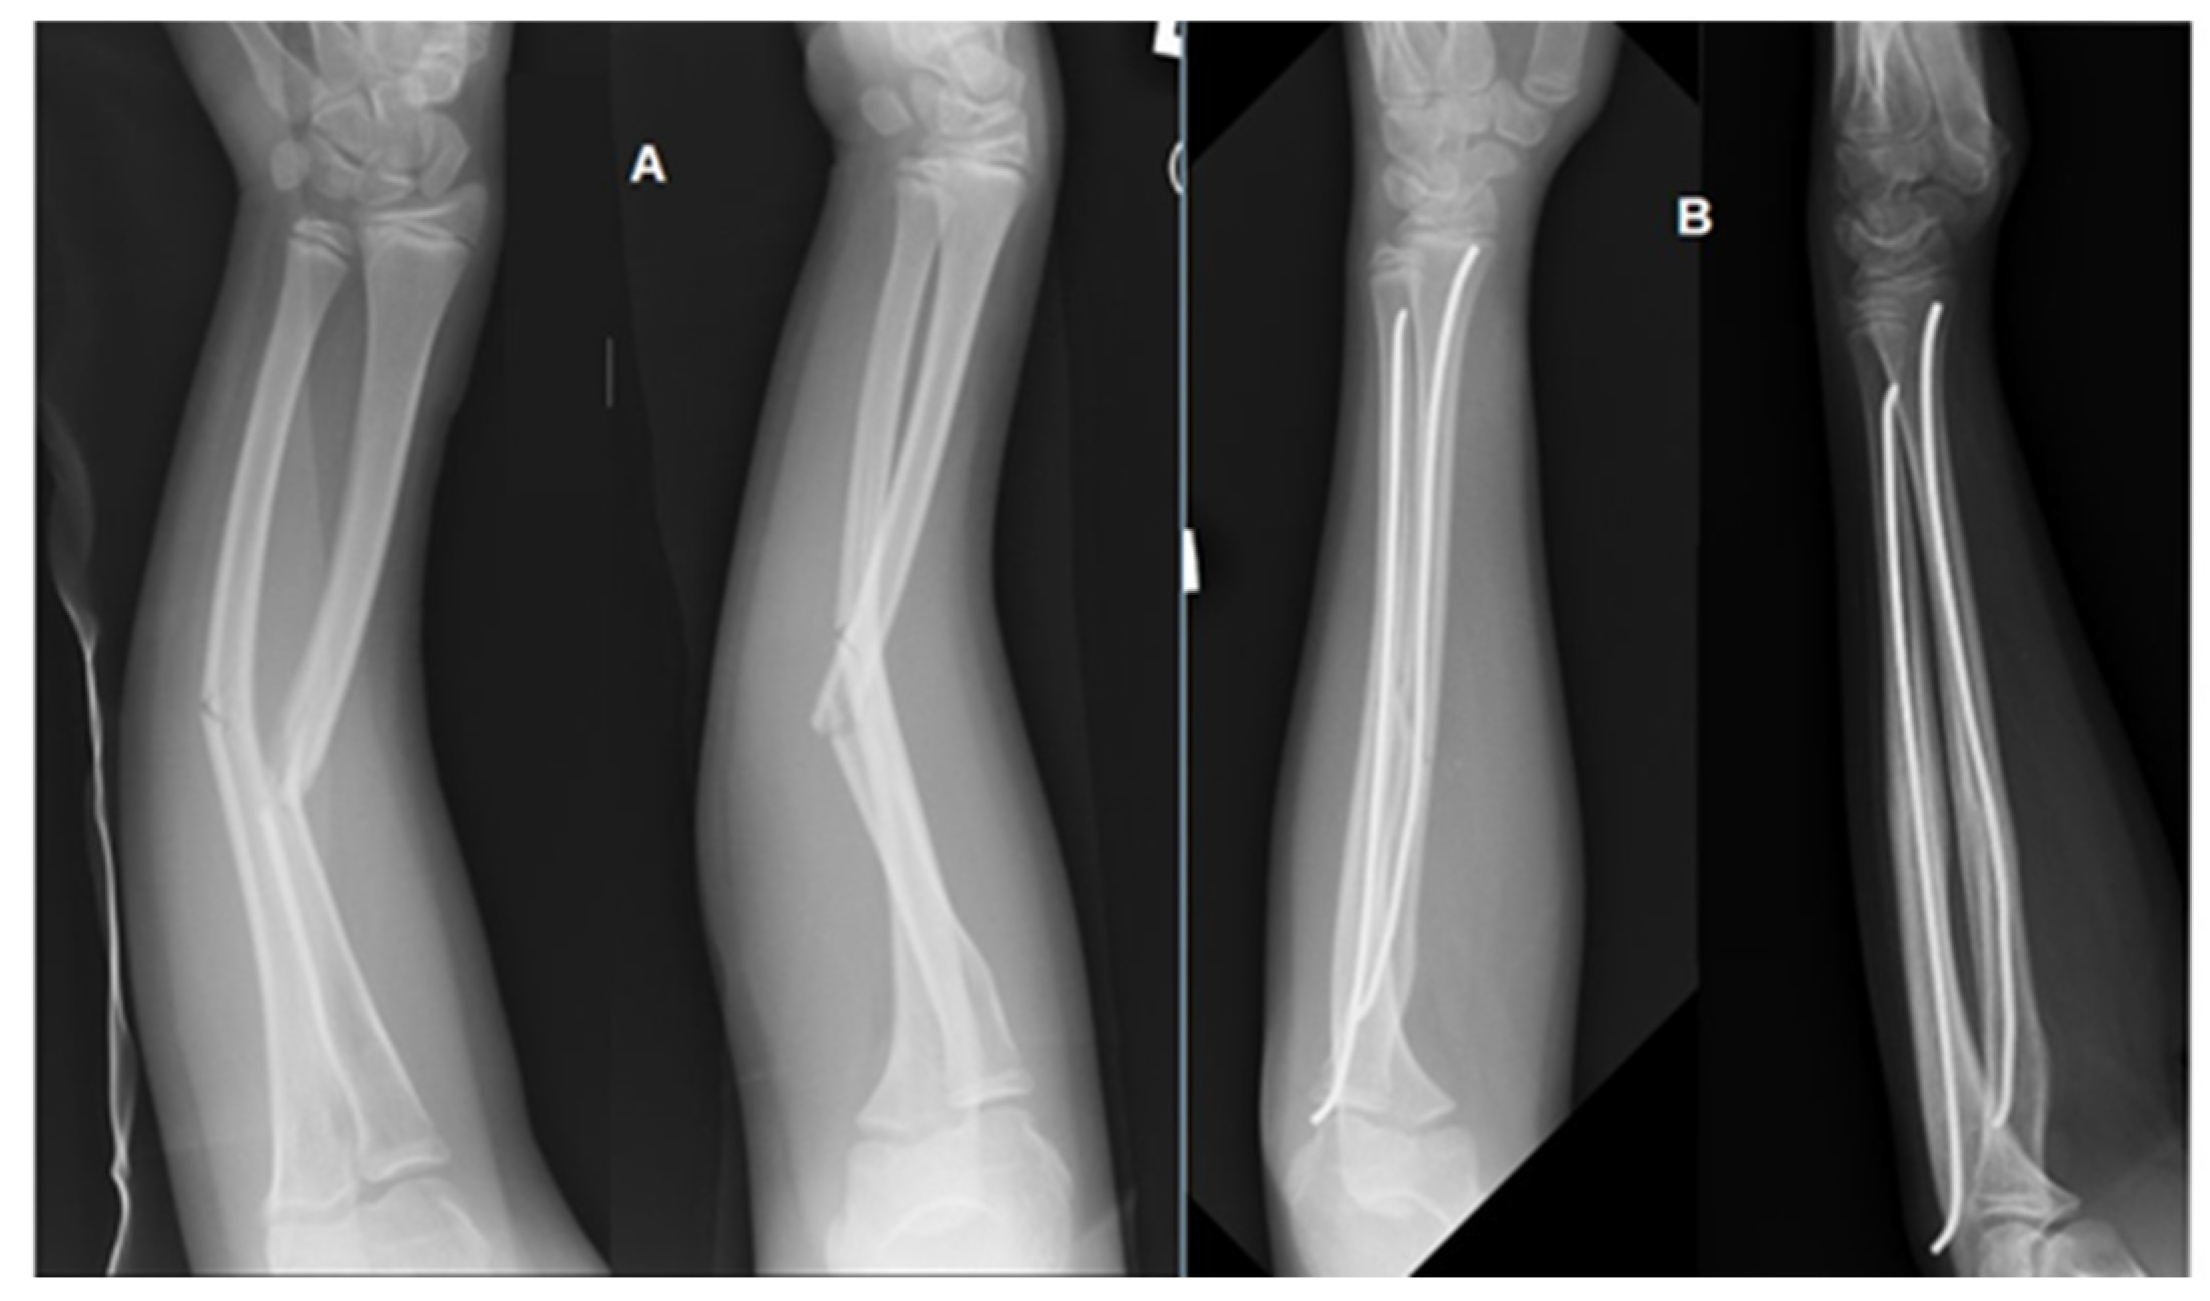

2. Materials and Methods

2.1. Participants of the Study

2.2. Research Material